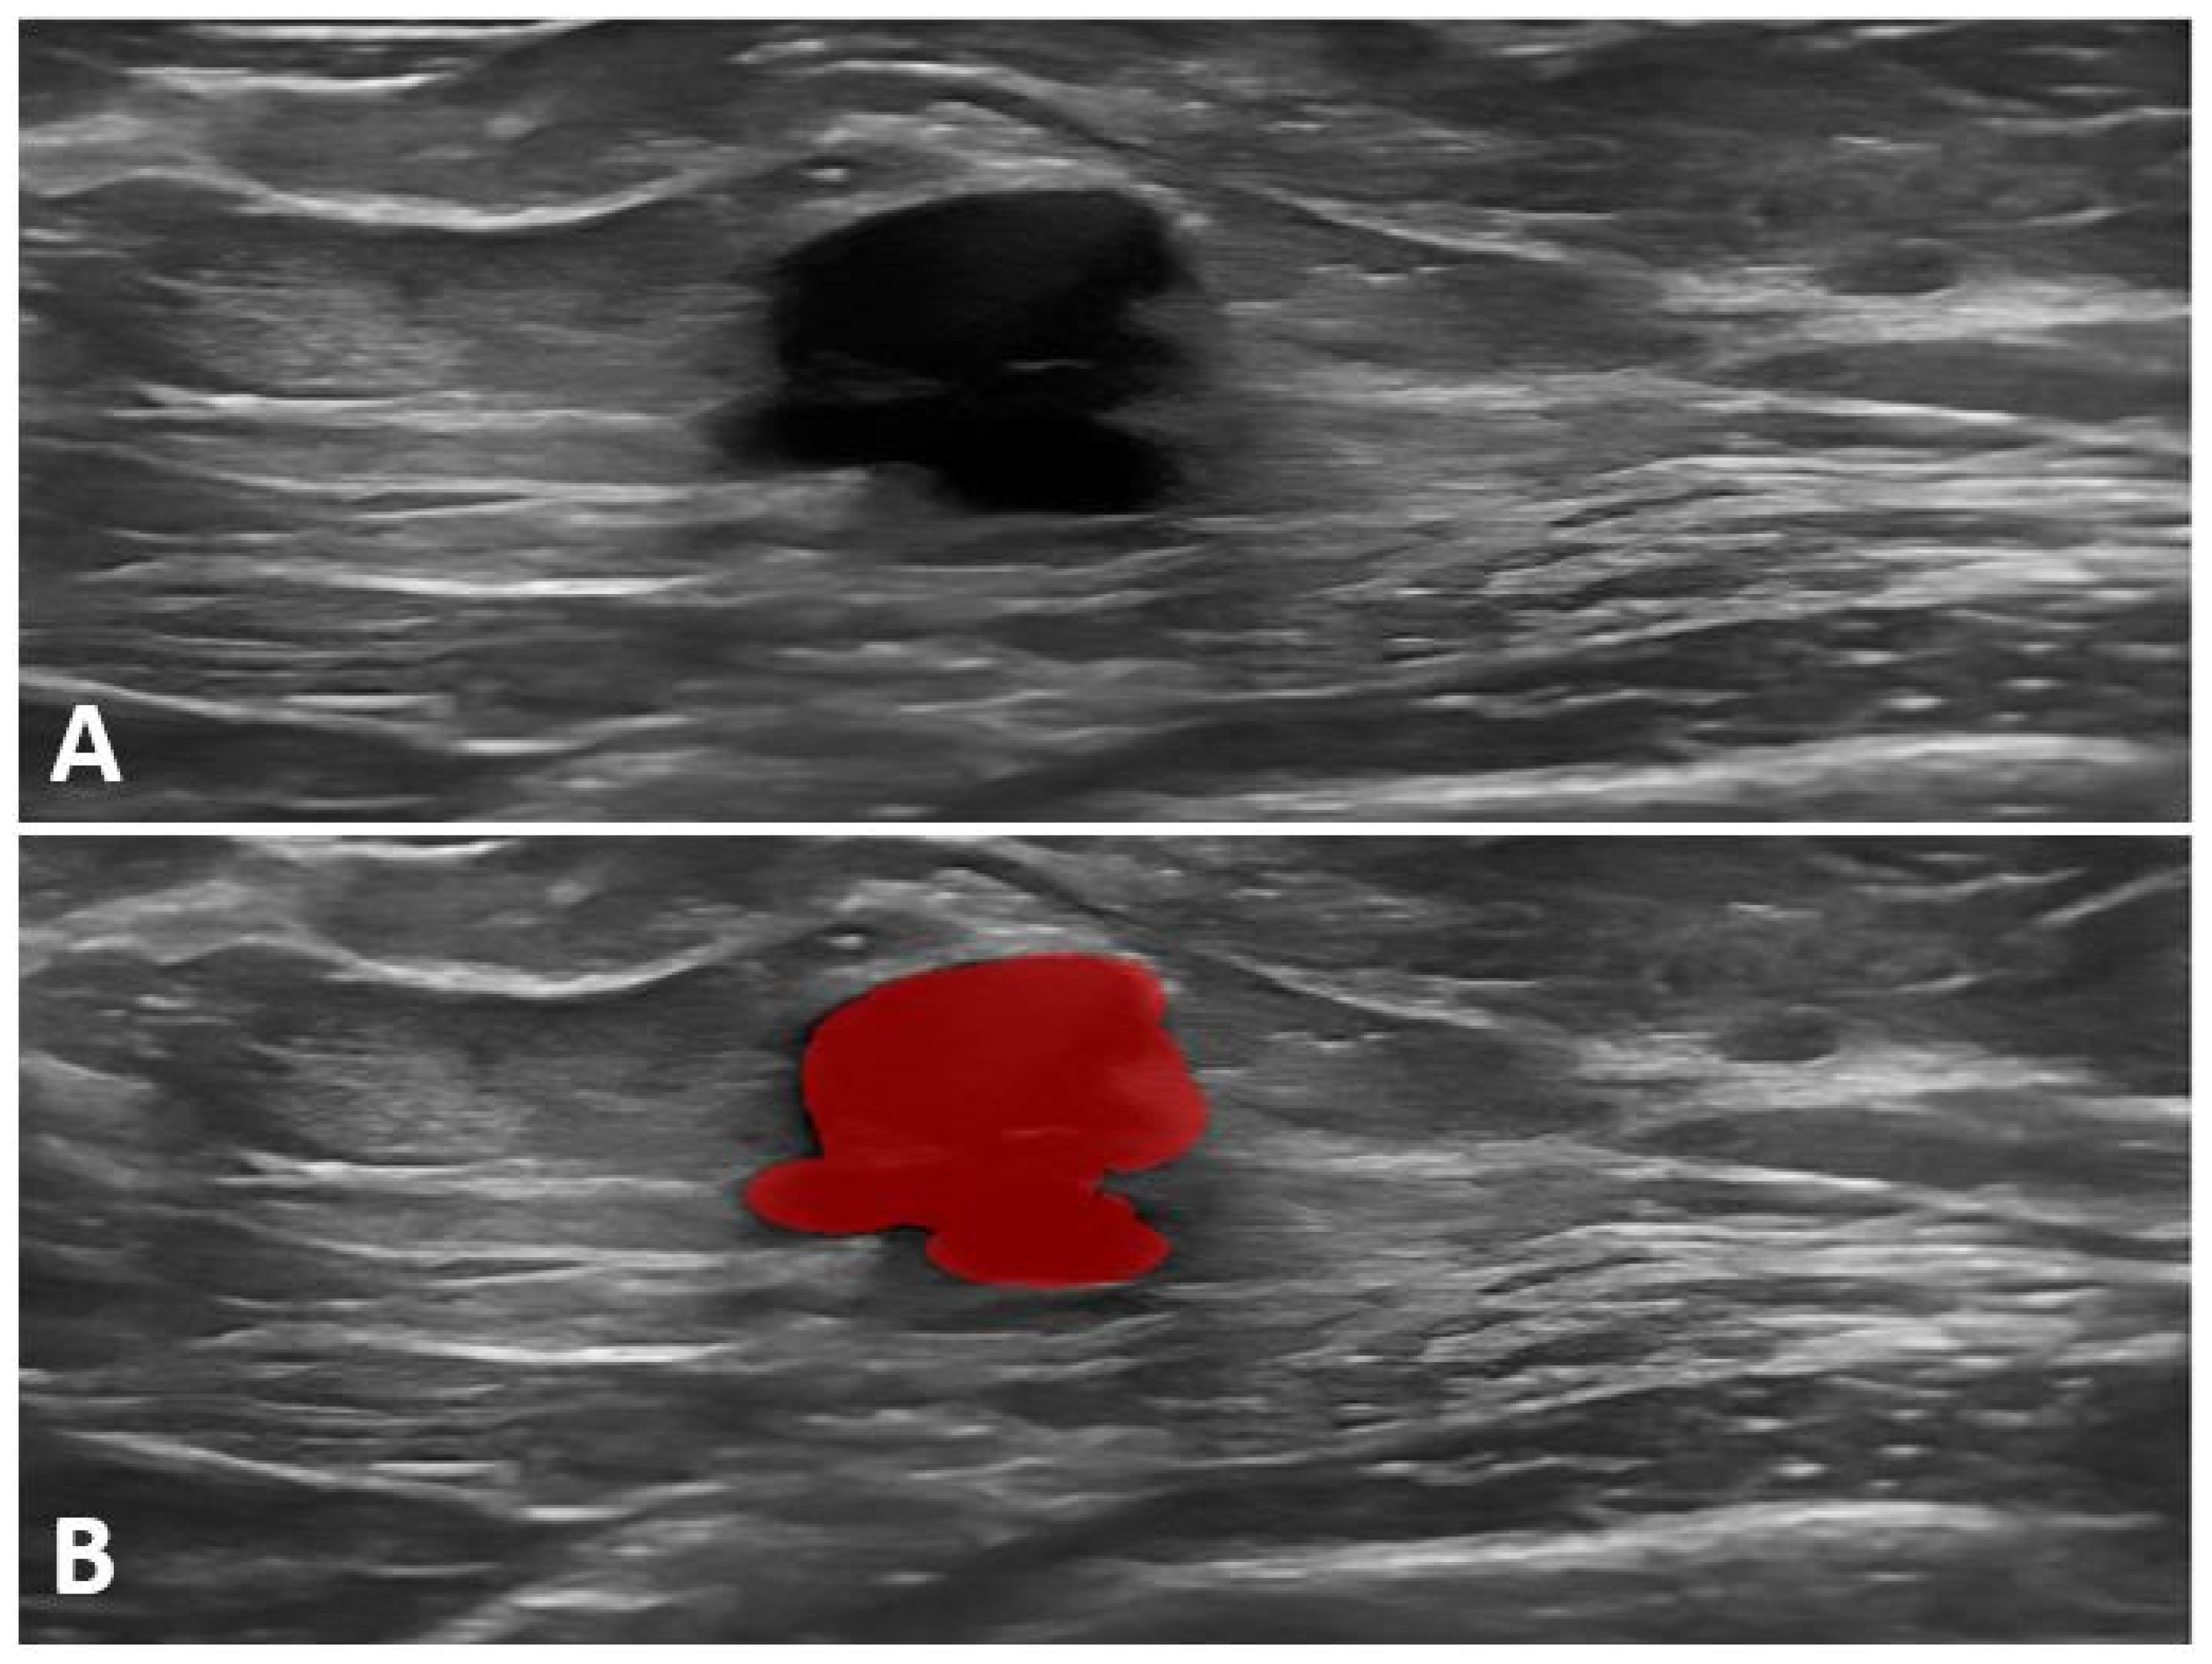

Figure 2.

BRCA1-positive patient. (A) Ultrasound image showing a hypoechoic, irregularly shaped mass with a partially microlobulated and indistinct margin. (B) Ultrasound image with segmented tumor area highlighted in red.